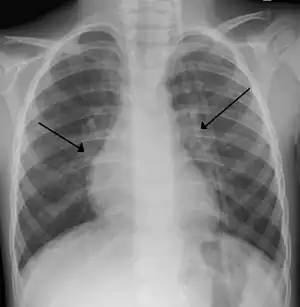

O diagnóstico é tipicamente feito por exame clínico. A radiografia de tórax é às vezes útil para excluir pneumonia bacteriana, mas não indicada em casos sinais de complicações ou fatores de riscos como prematuridade. PCR para identificar o vírus também não é feito de rotina.[10]